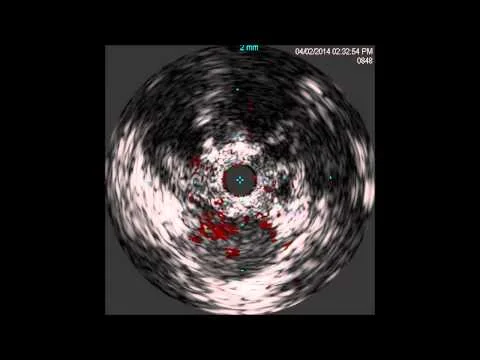

Eagle-Eye IVUS after Mustang PTA of LSFA